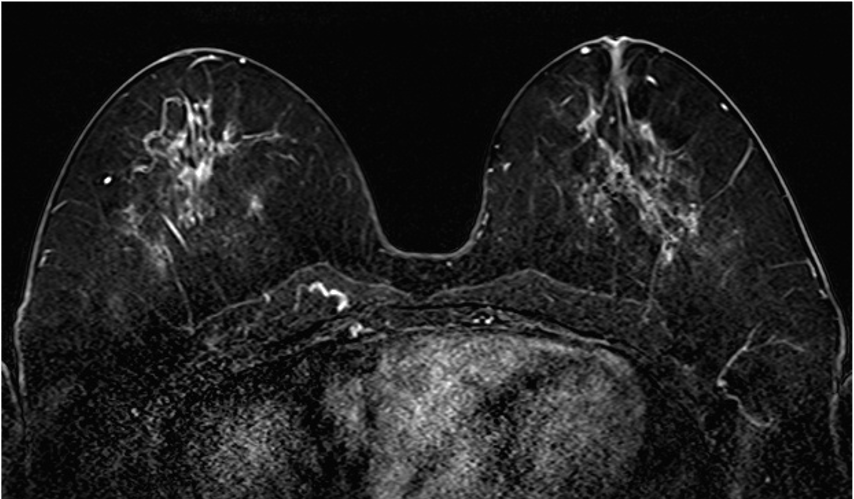

6. 造影後高分解能画像

BPEの影響が強く、観察が困難ではあるが、高分解能画像によって、内部性状(clumped)や分布(segmental)などのDCISの病変(矢印)の形態的性状がより鮮明に観察することができる。